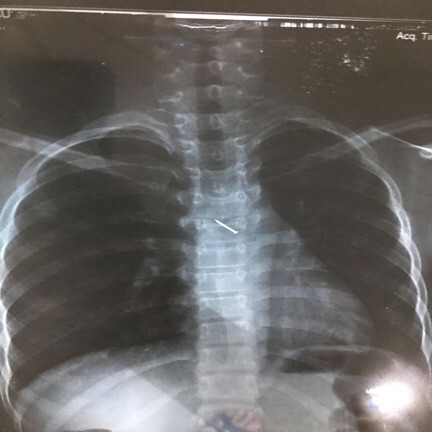

Từ ngày thứ 3 đến ngày thứ 7 của bệnh. Thời kỳ này tương ứng với thời kỳ virus xâm nhập vào tế bào não tuỷ gây huỷ hoại các tế bào thần kinh. Bước sang thời kỳ khởi phát các triệu chứng không giảm mà lại tăng lên bệnh nhân đi vào hôn mê sâu dần. Các triệu chứng rối loạn thần kinh thực vật cũng tăng lên như vã nhiều mồ hôi, da lúc đỏ, lúc tái, rối loạn nhịp thở và tăng tiết trong lòng khí quản do vậy khi nghe phổi có thể thấy nhiều ran rít, ran ngáy và cả ran nổ. Mạch thường nhanh và yếu. Thời kỳ toàn phát diễn ra ngắn bệnh nhân nhanh chóng rơi vào tình trạng hôn mê sâu với rối loạn các chức năng sống . Những bệnh nhân vượt qua được thời kỳ này thì tiên lượng tốt hơn.